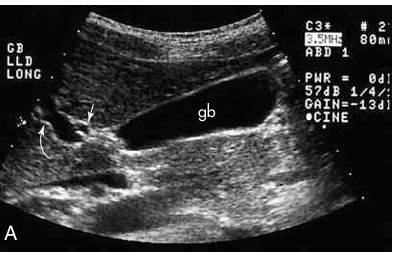

black: cystic duct

white: valves of heister

arrow is pointing to?

CBD

arrow: MLF

curved arrow: portal vein

what are the arrows pointing to?

cystic duct